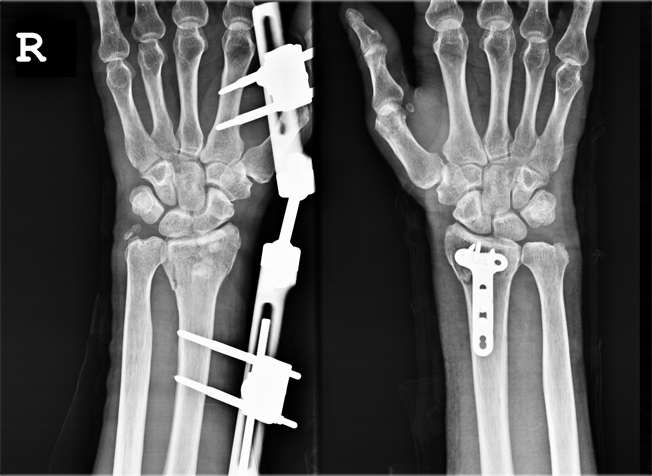

손목관절 골절

손목관절의 치료

x-ray 사진

요골성인골절